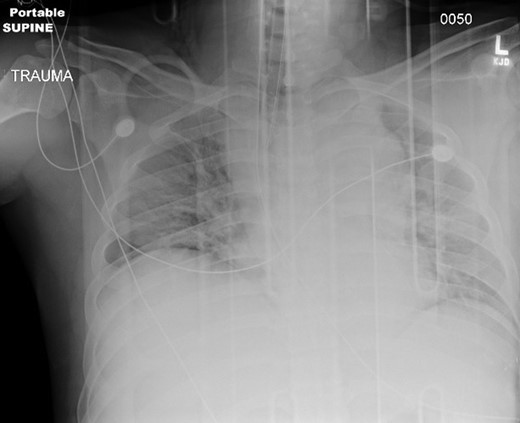

Chest, pelvis and right lower extremity X-rays were obtained. Chest X-ray findings are shown in Fig. 1. Pelvic X-ray was negative for acute injuries. Right lower extremity X-ray revealed the presence of a right tibia-fibula fracture and the right lower extremity was immobilized with a posterior splint.